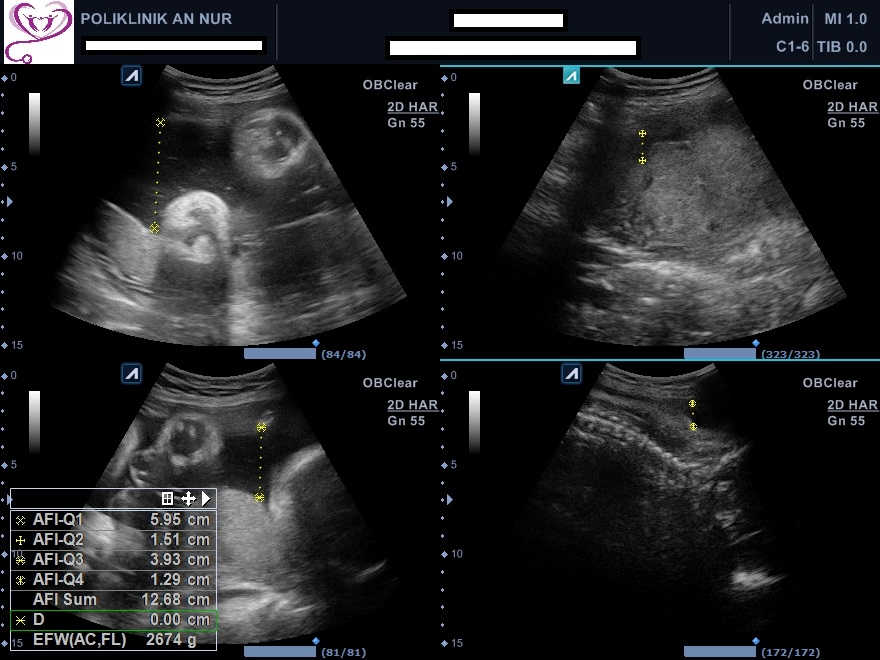

- Mengetahui kadar air ketuban sama ada mencukupi atau tidak

- Mengetahui panjang dan lebar bayi